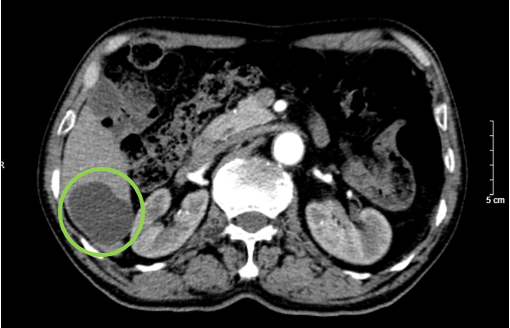

UNG THƯ BIỂU MÔ TẾ BÀO THẬN

Ung thư thận là loại ung thư thường gặp đứng thứ 14 trên toàn cầu, với hơn 430.000 ca mới được chẩn đoán vào năm 2020, và 434840 ca mắc trên toàn cầu vào năm 2022. Tỷ lệ mắc thay đổi theo khu vực địa lý, cao hơn ở châu Âu và Bắc Mỹ. Ung...